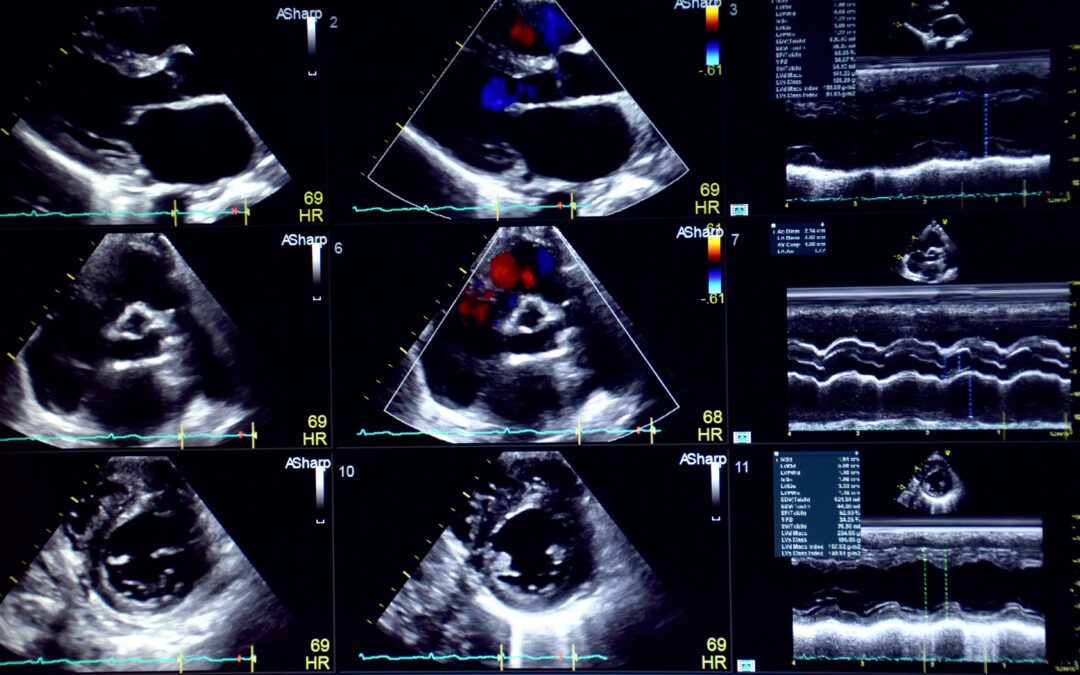

An echocardiogram, or echo, is a test that uses sound waves to create a picture of the heart while in motion. The results show the shape and size of the heart and reveal how the heart valves and chambers are functioning. Medicare will usually cover the test if it is...